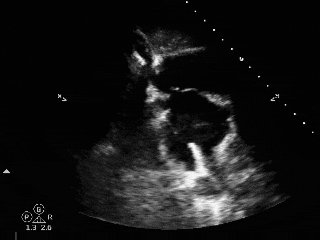

术前超声

超声描述:右房室较大,左房室不大。房间隔中部可见中断,约14x16mm。缺损边缘较硬,二尖瓣侧缘、后上缘分别为16mm、8mm,主动脉侧缘、后壁缘分别为0mm、10.7mm,上、下腔静脉侧缘分别为16、14mm。十字交叉存在。房间隔长度43mm。M型二尖瓣呈双峰,前后叶逆向,E-E间距相等。

CDFI:房水平可见一股红色彩流由左房经缺口进入右房。主动脉瓣下左室流出道探及微量舒张期反流信号。三尖瓣口右房侧探及微量收缩期反流信号,Vp 2.7m/s,PG 29mmHg。二尖瓣口左房侧探及微量收缩期反流信号。

超声提示:

先天性心脏病。

房间隔缺损(继发孔型)。

左心收缩功能在正常范围。